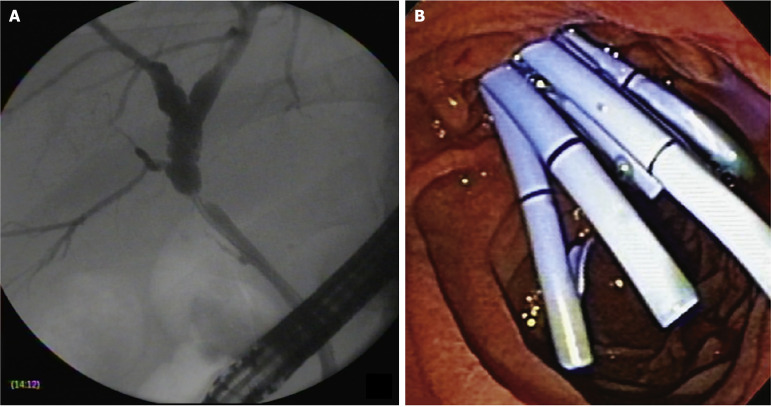

Background: Biliary anastomotic stricture (BAS) occurs in approximately 14%-20% of patients post-orthotopic liver transplantation (post-OLT). Endoscopic retrograde cholangiopancreatography (ERCP) using multiple plastic stents (MPSs) or fully covered self-expandable metal stents (cSEMSs) represent the standard treatment for BAS post-OLT. Recently, cSEMSs have emerged as the primary option for managing BAS post-OLT.

Methods: This retrospective cohort study was conducted in a single tertiary care center (Hospital Israelita Albert Einstein, São Paulo, Brazil). We reported the results of endoscopic therapy in patients with post-OLT BAS between 2012 and 2022. Patients were stratified into two groups according to therapy: (1) MPSs; and (2) cSEMSs. Primary endpoints were to compare stricture resolution and recurrence among the groups. The secondary endpoint was to identify predictive factors for stricture recurrence.

Results: A total of 104 patients were included. Overall stricture resolution was 101/104 (97.1%). Stricture resolution was achieved in 83/84 patients (99%) in the cSEMS group and 18/20 patients (90%) in the MPS group (P = 0.094). Failure occurred in 3/104 patients (2.8%). Stricture recurrence occurred in 9/104 patients (8.7%). Kaplan-Meier analysis showed there was no difference in recurrence-free time among the groups (P = 0.201). A multivariate analysis identified the number of ERCP procedures (hazard ratio = 1.4; 95% confidence interval: 1.194-1.619; P < 0.001] and complications (hazard ratio = 2.8; 95% confidence interval: 1.008-7.724; P = 0.048) as predictors of stricture recurrence.

Conclusion: cSEMSs and MPSs were effective and comparable regarding BAS post-OLT resolution and recurrence. The number of ERCP procedures and complications were predictors of stricture recurrence.